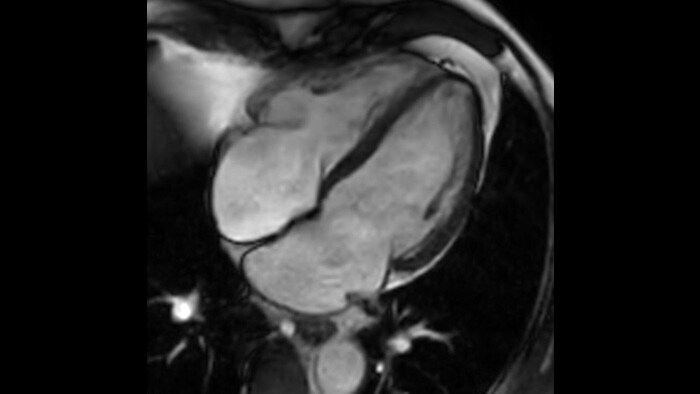

Діагностична точність Розширте свої можливості візуалізації в усіх клінічних областях. Дізнайтеся, які переваги отримують ваші колеги.

Магніт Ingenia Ambition із напруженістю поля 1,5 Тл є наступним поколінням МРТ-технологій. Він поєднує в собі найголовніші риси, що характеризують ефективну МРТ-систему.